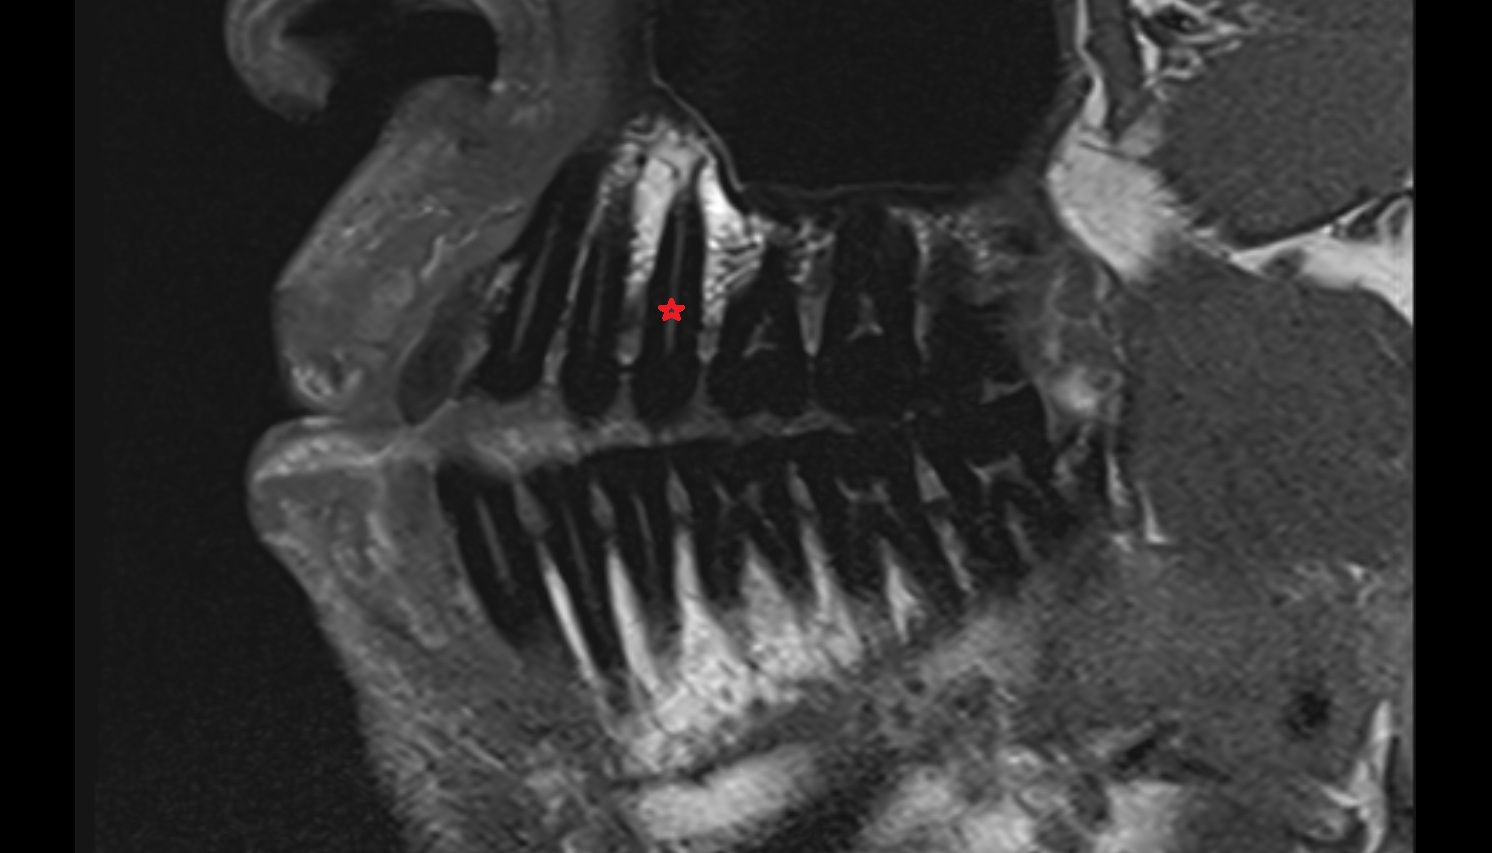

- Root of lower molar tooth

- Lower molar apical foramen

- Upper premolar apical foramen

- Root of upper molar tooth

- Root canal of upper molar tooth

- Dental pulp of upper molar tooth

- Dental pulp of upper premolar tooth

- Enamel of lower molar tooth

- Enamel of upper molar tooth

- Dental pulp of lower molar tooth

- Root canal of lower premolar tooth

- Lower premolar apical foramen

- Dental branches of inferior alveolar artery, vein, & nerve

- Alveolar process of maxilla

- Superior dental plexus